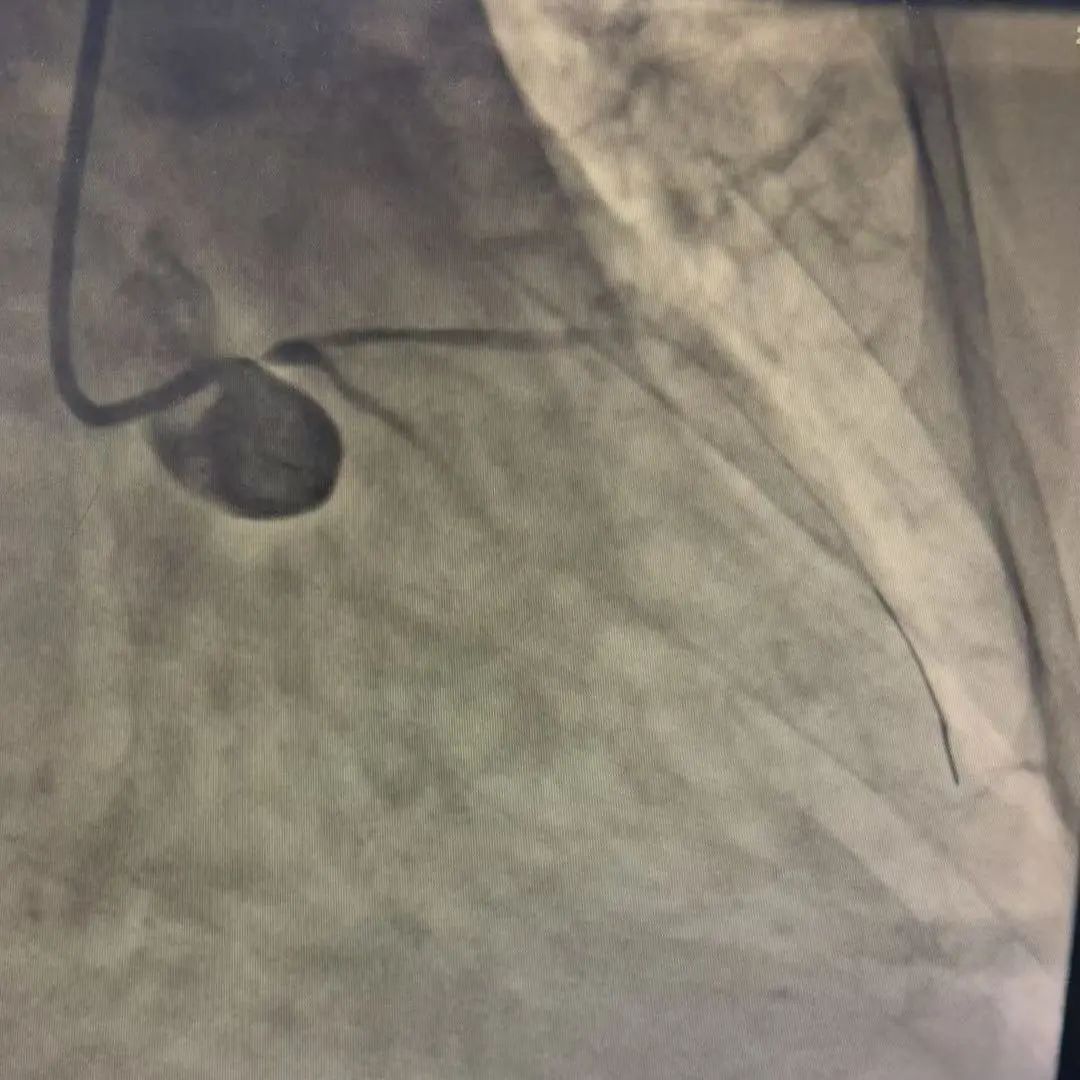

患者术前冠脉造影

凌晨2:30,在主动脉内球囊反搏术(IABP)支持下,为患者实施急诊冠脉造影(CAG)及PCI手术。术中造影显示:左主干开口至左主干本体100%闭塞,前向TIMI血流0级,右冠中段可见60%狭窄,PL近段局部90%狭窄。